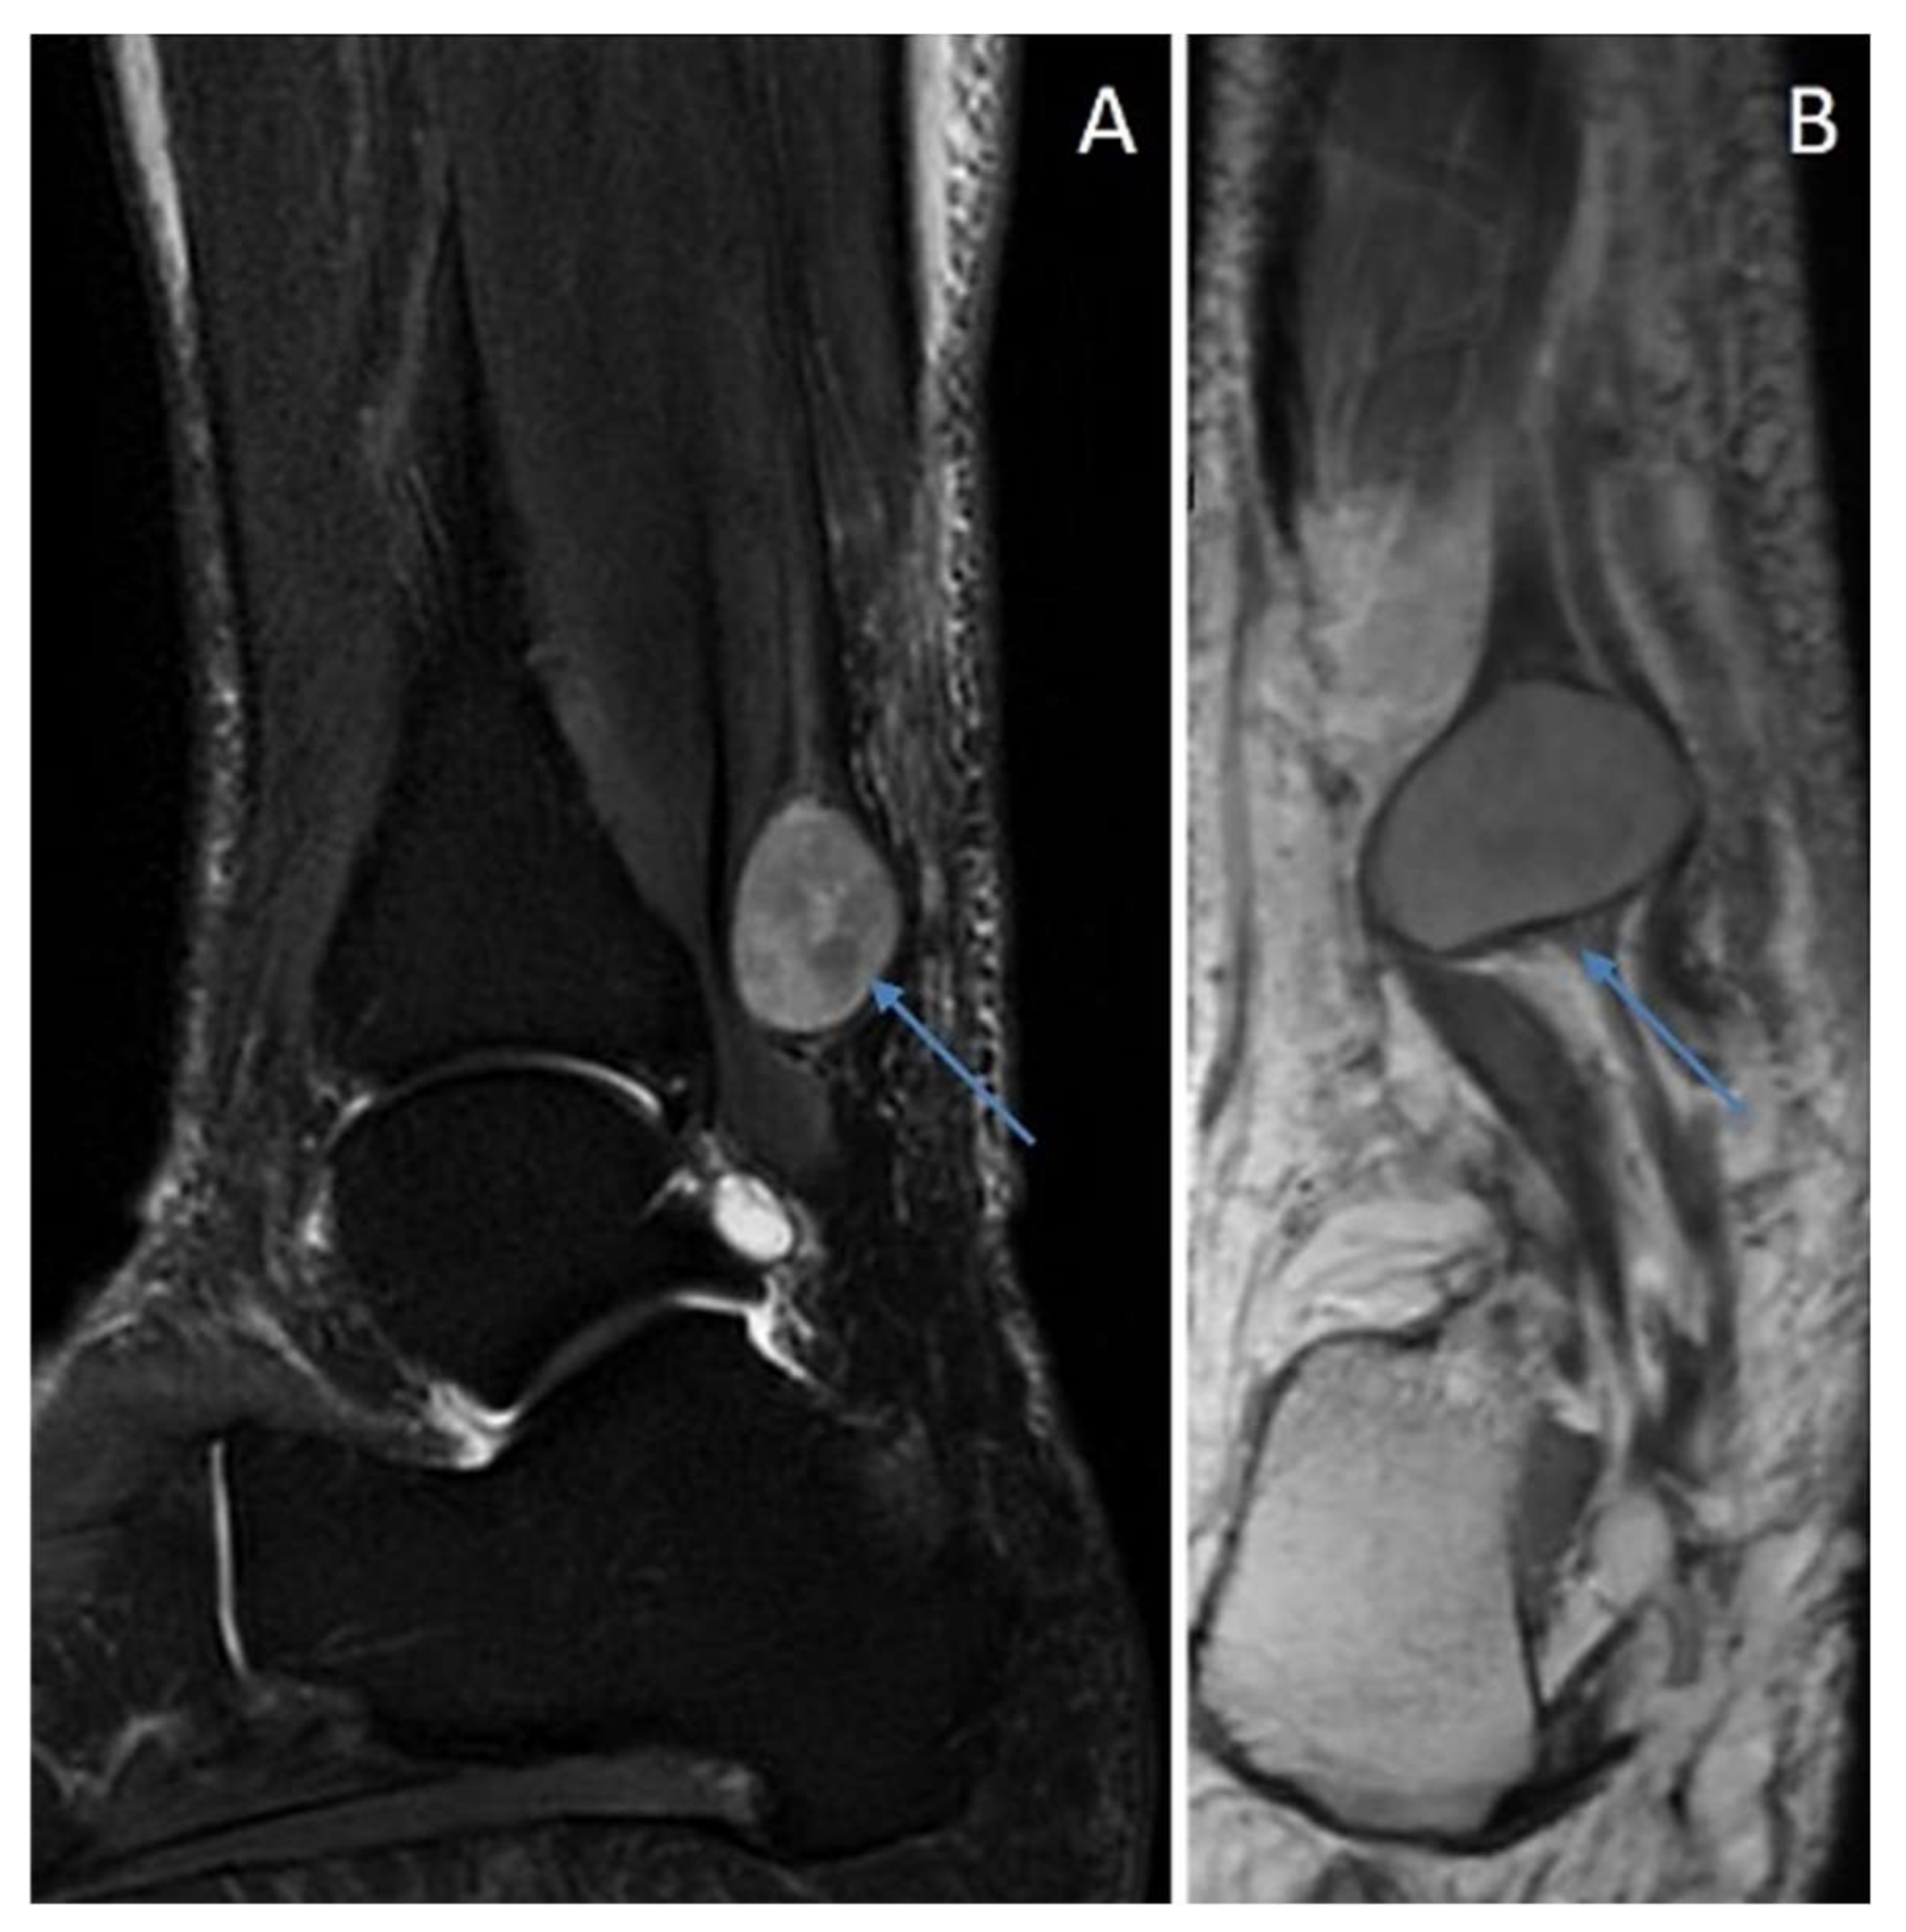

6.3. Cellular Schwannoma

Immunohistochemical Features